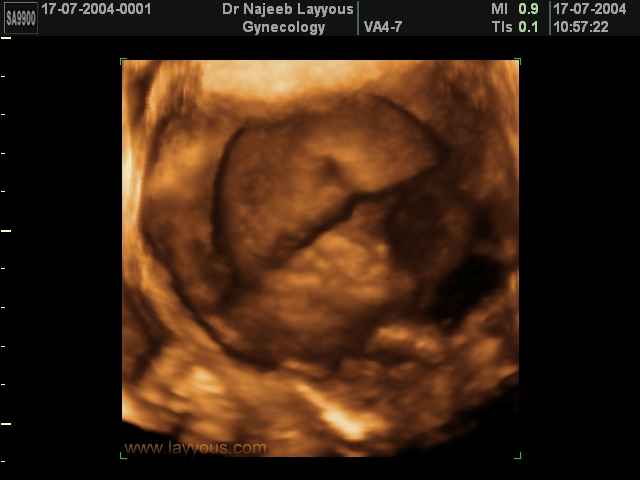

- صور للجنين في المراحل الأولى من الحمل